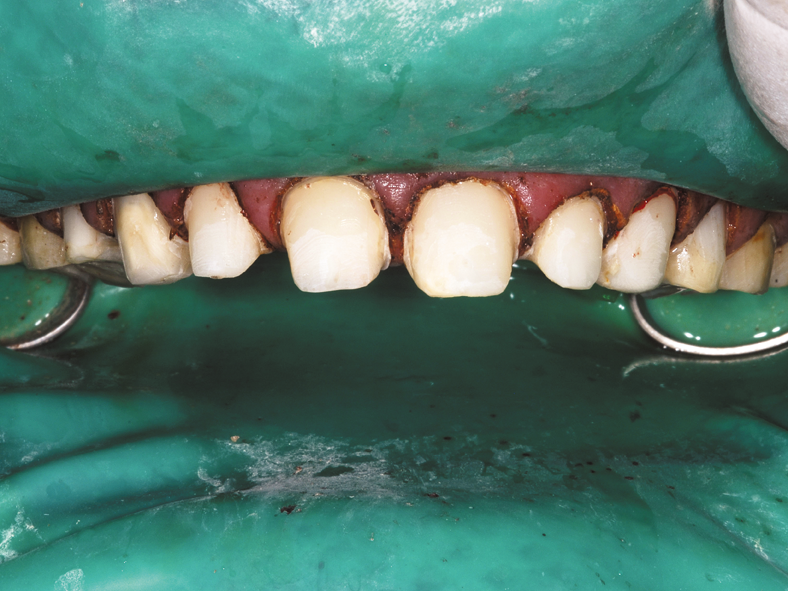

Fig. 1 Fig. 3

This clinical case demonstrates the use of CORE-FLO DC LITE with Bisco’s dual-cured UNIVERSAL PRIMER for post and core build-ups. The patient presented with advanced decay in multiple teeth. He was a relatively healthy 30-year-old male with a history of drug and alcohol abuse. He had recently completed a substance abuse rehabilitation program and wanted to finish his dental treatment.

He stopped his prior dental treatment while still in his temporary restorations. He eventually lost the temporaries and went without for several years. As a result he was left with extensive decay in the previously prepared anterior teeth (Figs. 1, 3).

On the maxillary preparation day the entire upper arch was anesthetized with articaine with 1:100,000 epinephrine and a full arch rubber dam placed (Fig. 4). The severely damaged anterior teeth #7-11 were cleaned and shaped for gutta percha final fill, then prepared for the fiber core posts (Fig. 5). Bisco’s dual-cured UNIVERSAL PRIMER was placed and agitated for 30 seconds on all five teeth at once.